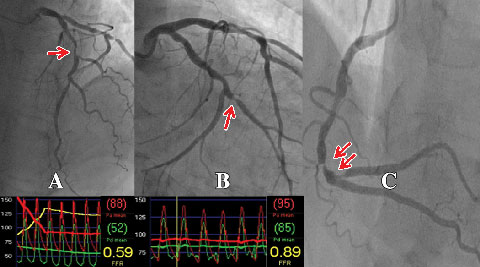

An important recent advance has been the ability to accurately determine the physiological significance of an individual coronary lesion by measuring FFR.7,15 FFR is defined as the ratio between coronary pressure distal to the stenosis in question and aortic pressure measured simultaneously during adenosine-induced hyperaemia. Coronary pressure is obtained by passing a pressure guide wire distal to the coronary stenosis in a manner analogous to passing a guide wire for the purpose of PCI.7,15 As such, it can be easily and safely performed by those experienced in performing PCI. If PCI is indicated as a result of the FFR measurement, the coronary pressure wire can be used for stent delivery. In the case of multiple lesions in one or more vessels, each individual lesion can be examined by the pressure wire (Box 2). In this way, the lesion or lesions causing ischaemia can be determined in a more precise manner than the traditional method of correlating the angiographic findings with the results of stress testing, or by using angiographic criteria alone.

A wealth of data has validated the accuracy of FFR as a measure of myocardial ischaemia.7,15,19 An FFR value of ≤ 0.80 identifies ischaemia-causing coronary stenoses with an accuracy of greater than 90%. An FFR > 0.80 excludes ischaemia with a predictive accuracy of 95%.15